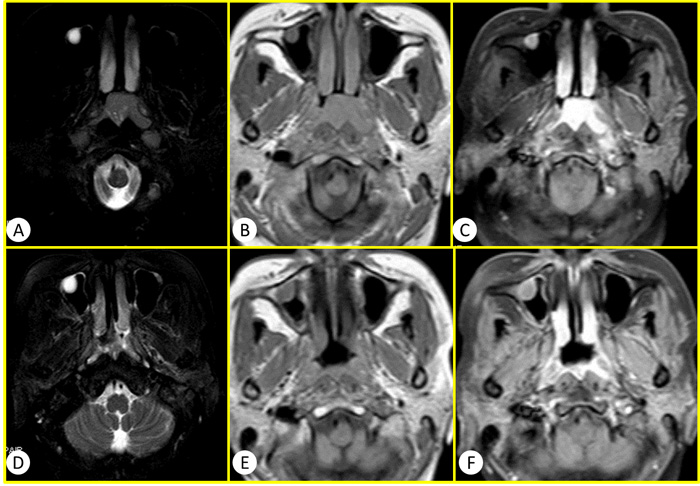

General MRI and IVIM were successfully performed in the 60 patients using 3.0-T whole-body system (Signa EXCITE HD, GE Healthcare, Milwaukee, WI, USA) before and after standard regimen of IMRT. The images of general MR sequence were showed in Figure 1. IVIM images and representative pathological slides of biopsy for both effective groups and poor effective groups were showed in Figure 2. The mean largest diameters of tumor (± SD) in patients with NPC before and after IMRT were showed in Figure 3, respectively.

Figure 1: The conventional MR images of a 50 years old woman diagnosed as NPC. A.-C. were before the therapy of IMRT and D.-F. were after the therapy of IMRT. A and D were T2WI SPAIR. B and D were T1WI. C and F were T1WI enhanced. Compared with the images before IMRT, the longest diameter of tumor lesion was obviously diminish >50% after the therapy of IMRT. Therefore this case was sort into the effective group with PR according to the RECIST standard.